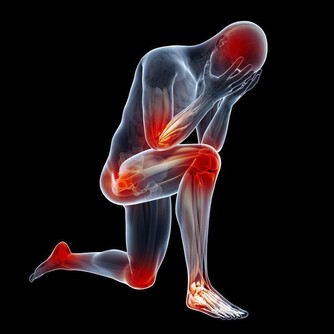

不同的情緒對應著不同的身體疾病。比如恐懼、焦慮會導致腹部疼痛;批評、內疚引發關節炎;

壓抑導致哮喘;經常憤怒的人容易有口臭,還愛發生膿腫;恐懼會引發暈車和痛經。

大量臨床醫學研究表明,小到感冒,大到冠心病和癌症,都與情緒有著密不可分的關係。

充滿心理矛盾、壓抑,經常感到不安全和不愉快的人,免疫力低下,經常感冒、一著急就喉嚨痛;緊張的人則會頭痛、血壓升高,容易引發心血管疾病;經常忍氣吞聲的人得癌症的機率是一般人的三倍。